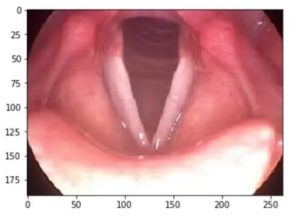

Узлы на голосовых связках симптомы

Узелки на ых связках — серьезное нарушение, которое часто встречается у людей в той или иной период жизни. Патологии, связанные с ым аппаратом, нередко наблюдаются у людей, которые вынуждены много петь и говорить. Причины появления подобной проблемы могут быть разными. Одной из самых распространенных считается нарушение функционирования фонационного дыхания и артикуляции.

Представляет собой небольшие пасма, которые симметрично расположены по краям ых складок образования, состоящие из фиброзной ткани. Если говорить о морфологии, узелки не являются опухолью.

Певческие узелки достаточно легко отличить от других образований гортани, поскольку эти «бугорки» расположены симметрично.

При длительном течении болезни они приобретают белый цвет.